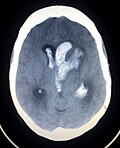

脳出血(のうしゅっけつ、英: Intracerebral hemorrhage; ICH)とは、頭蓋内の出血病態の総称であり、一般には脳溢血として広く知られている。脳出血は脳内への出血が起こる狭義の脳内出血と、主に脳動脈瘤の破裂によって生じるクモ膜下出血に分類される。医学的には狭義での脳内出血のみを指すことがある。…

4キロバイト (457 語) - 2025年4月24日 (木) 21:18

渋谷陽一さんは2023年に脳出血を発症し、しばらく療養とリハビリに取り組んでいました。渋谷さんは音楽に対する熱い情熱を抱き続け、最後の時までその信念を貫いていました。療養中も音楽業界に対する影響力を失わず、多くの人々にその存在感を示し続けました。残念ながら、彼は療養中に誤嚥性肺炎を併発し、74歳で亡くなりました。しかし、その死は多くのファンと音楽業界の関係者に多大な悲しみと喪失感をもたらしました。